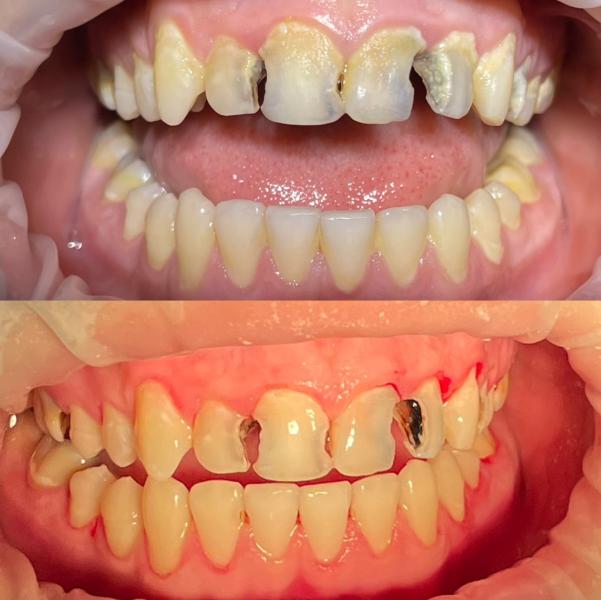

Брезгливым не листать ❌❌❌

Пациент 16лет,мама впервые привела к стоматологу,в полости рта очень плачевное состояние,объяснила маме все,расписала лечение провела проф гигиену(убрала весь налет и камни)

Далее мама отказалась от лечения,говоря что это очень дорого

Что я могу тут сказать?Мне очень жаль мальчика..их лечение не обходилось бы им в такую сумму,если бы она приводила его 2раза в год на санацию,очень надеюсь что они не оставят все так и будут лечить хотя бы один/два зуба в месяц